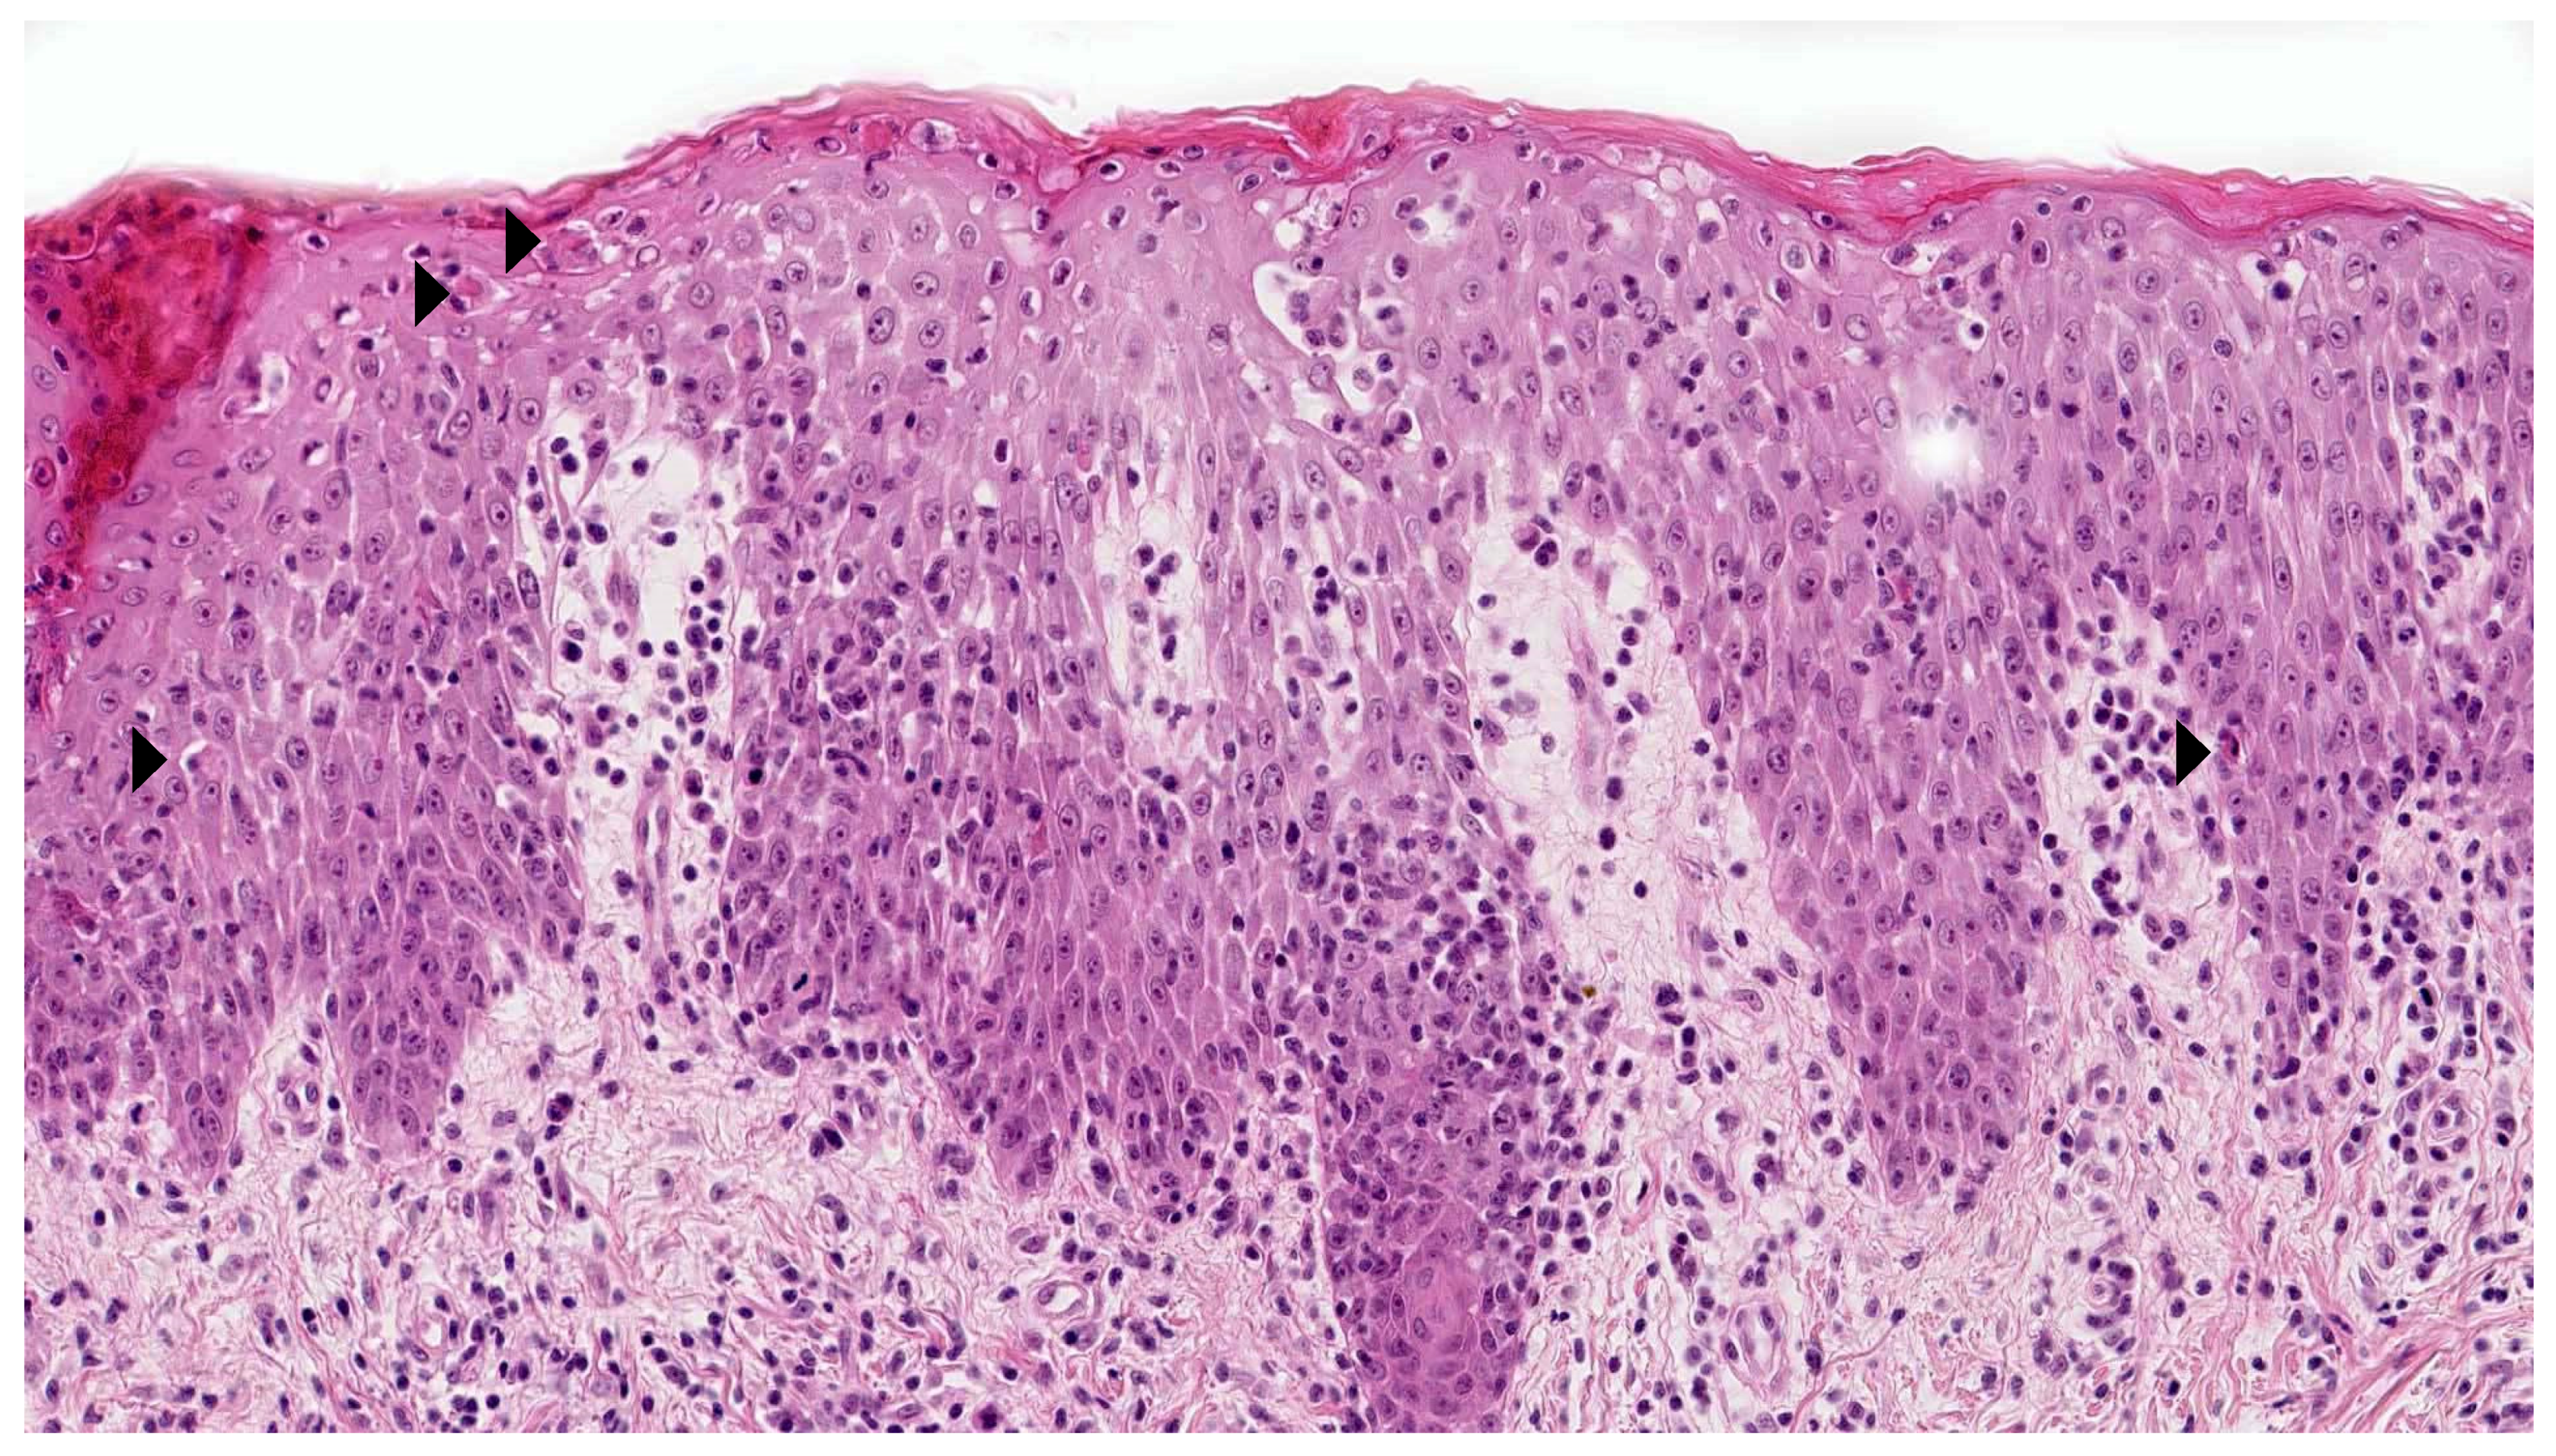

2.1. Vitiligo